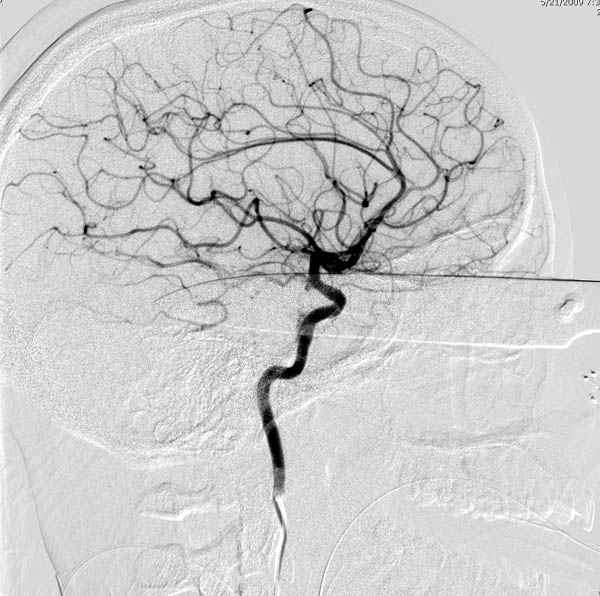

По протоколу сделаны все необходимые исследования: рентген, ангиограмма с 3Д реконструкцией, где обнаружили что все жизненно важные сосуды не задеты, даже некоторые "сидят" изгибаясь на ноже.

Одним махом нож удалить не удалось, пришлось раскачать и потом двумя руками удалили нож. Рана без кровотечения, обработана и зашита.